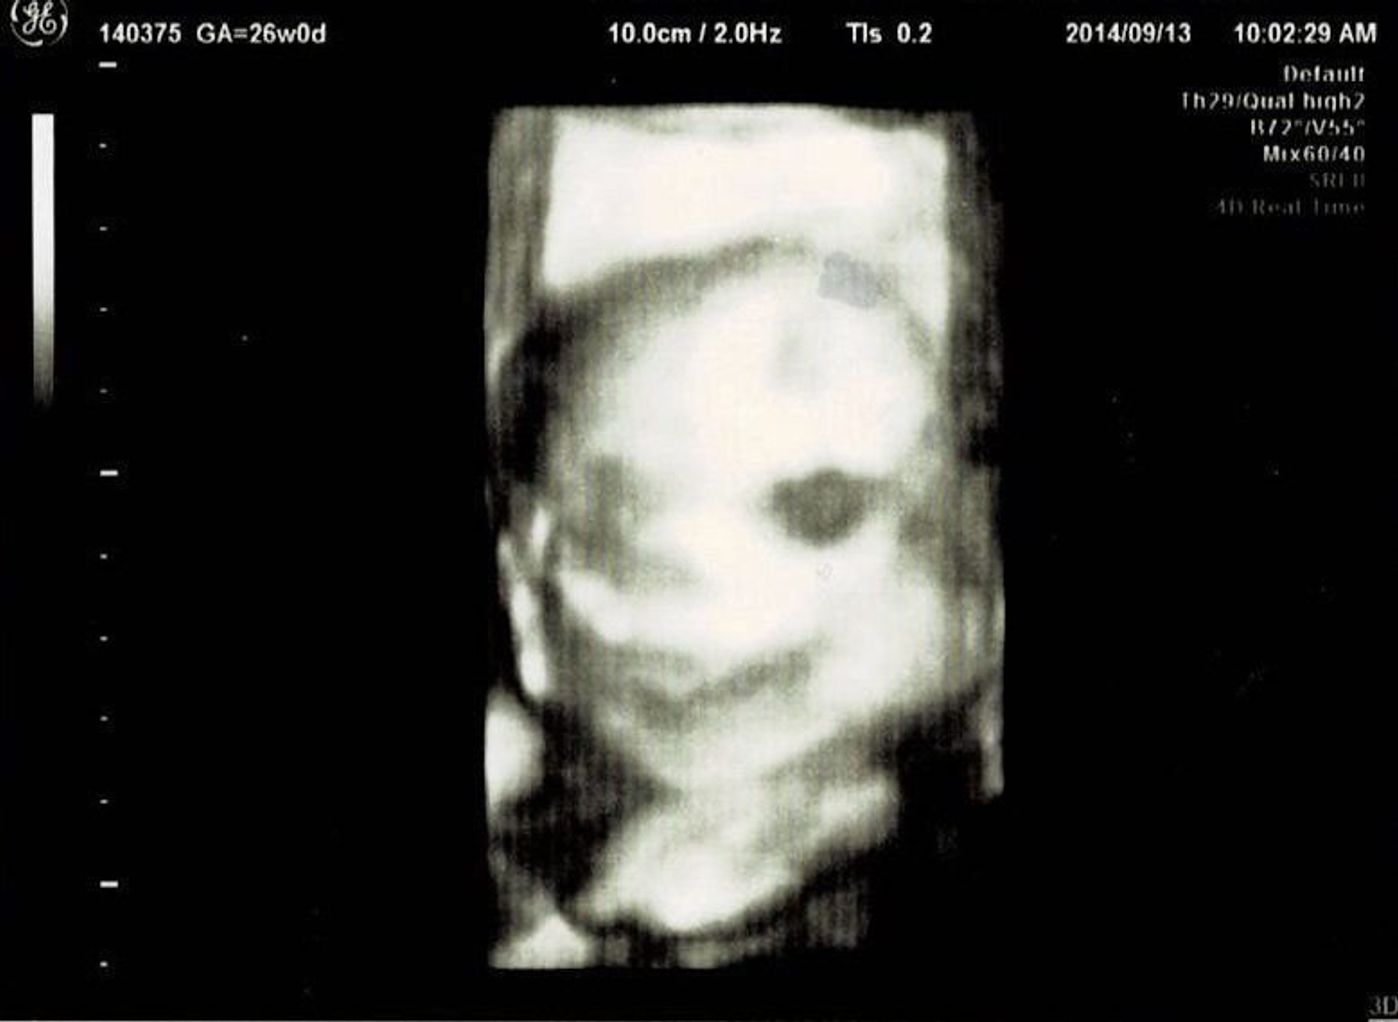

エコー 写真 と 実際 の 顔 比較- 出産前は、4dエコー(3dエコー)の写真を見つめながら、まだ見ぬわが子に思いを馳せたものです。 実際、エコー写真と産まれた後の顔は似ているのか? 4dエコー(24週・27週)/3dエコー(36週)と生後3日の写真を比較してみました。 スポンサーリンク3Dエコーとの違いや料金などまとめ 妊娠10週のエコーで性別やダウン症は自分でも highclass 画像ありエコー写真と実際の顔を徹底比較!!4Dエコー撮影 妊娠16週目(16w0d~6d)のエコー写真と 4dエコーと実際の顔を生後7日間の徹底比較!画像で検証

私のエコー写真を見てみると4Dエコーなどのお写真を撮る時は 25週から27週あたりが1番実際のお顔に近い んじゃないかなと思いました(^^) 出産に近付くと見えにくくなりますし、とってもぶちゃいくにうつりますw ↑実際の顔写真と3Dを比較 エコー写真すごい。